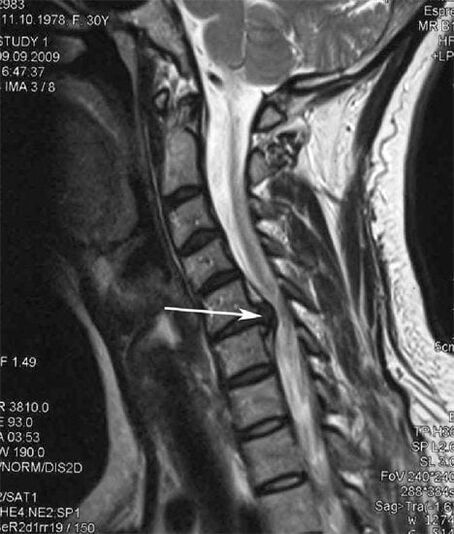

In the initial stage, osteochondrosis is detected using MRI.Later, the pathology can be diagnosed using radiography.A decrease in the distance between the vertebrae, pathological changes in the facet joints, and osteophytosis can be noticed on X-rays of the cervical spine.

Many people complain that they cannot turn their neck due to severe pain that occurs when they suddenly lift it.This phenomenon indicates the development of a herniated disc.The cause of pain in the back, neck and upper limb is pinching of one of the nerve roots exiting the spinal cord.

| Cervical osteochondrosis | The appearance of pathological changes in one or more spinal movement segments.Impairment of spinal mobility, development of myofascial pain syndromes and pinching of spinal roots | Pain, paresthesia and motor disturbances in the neck region, spreading to the back of the head and upper limbs.Detection of characteristic changes in the spine on MRI and X-rays (osteophytes, reduced vertebral distance, signs of damage to intervertebral joints) |